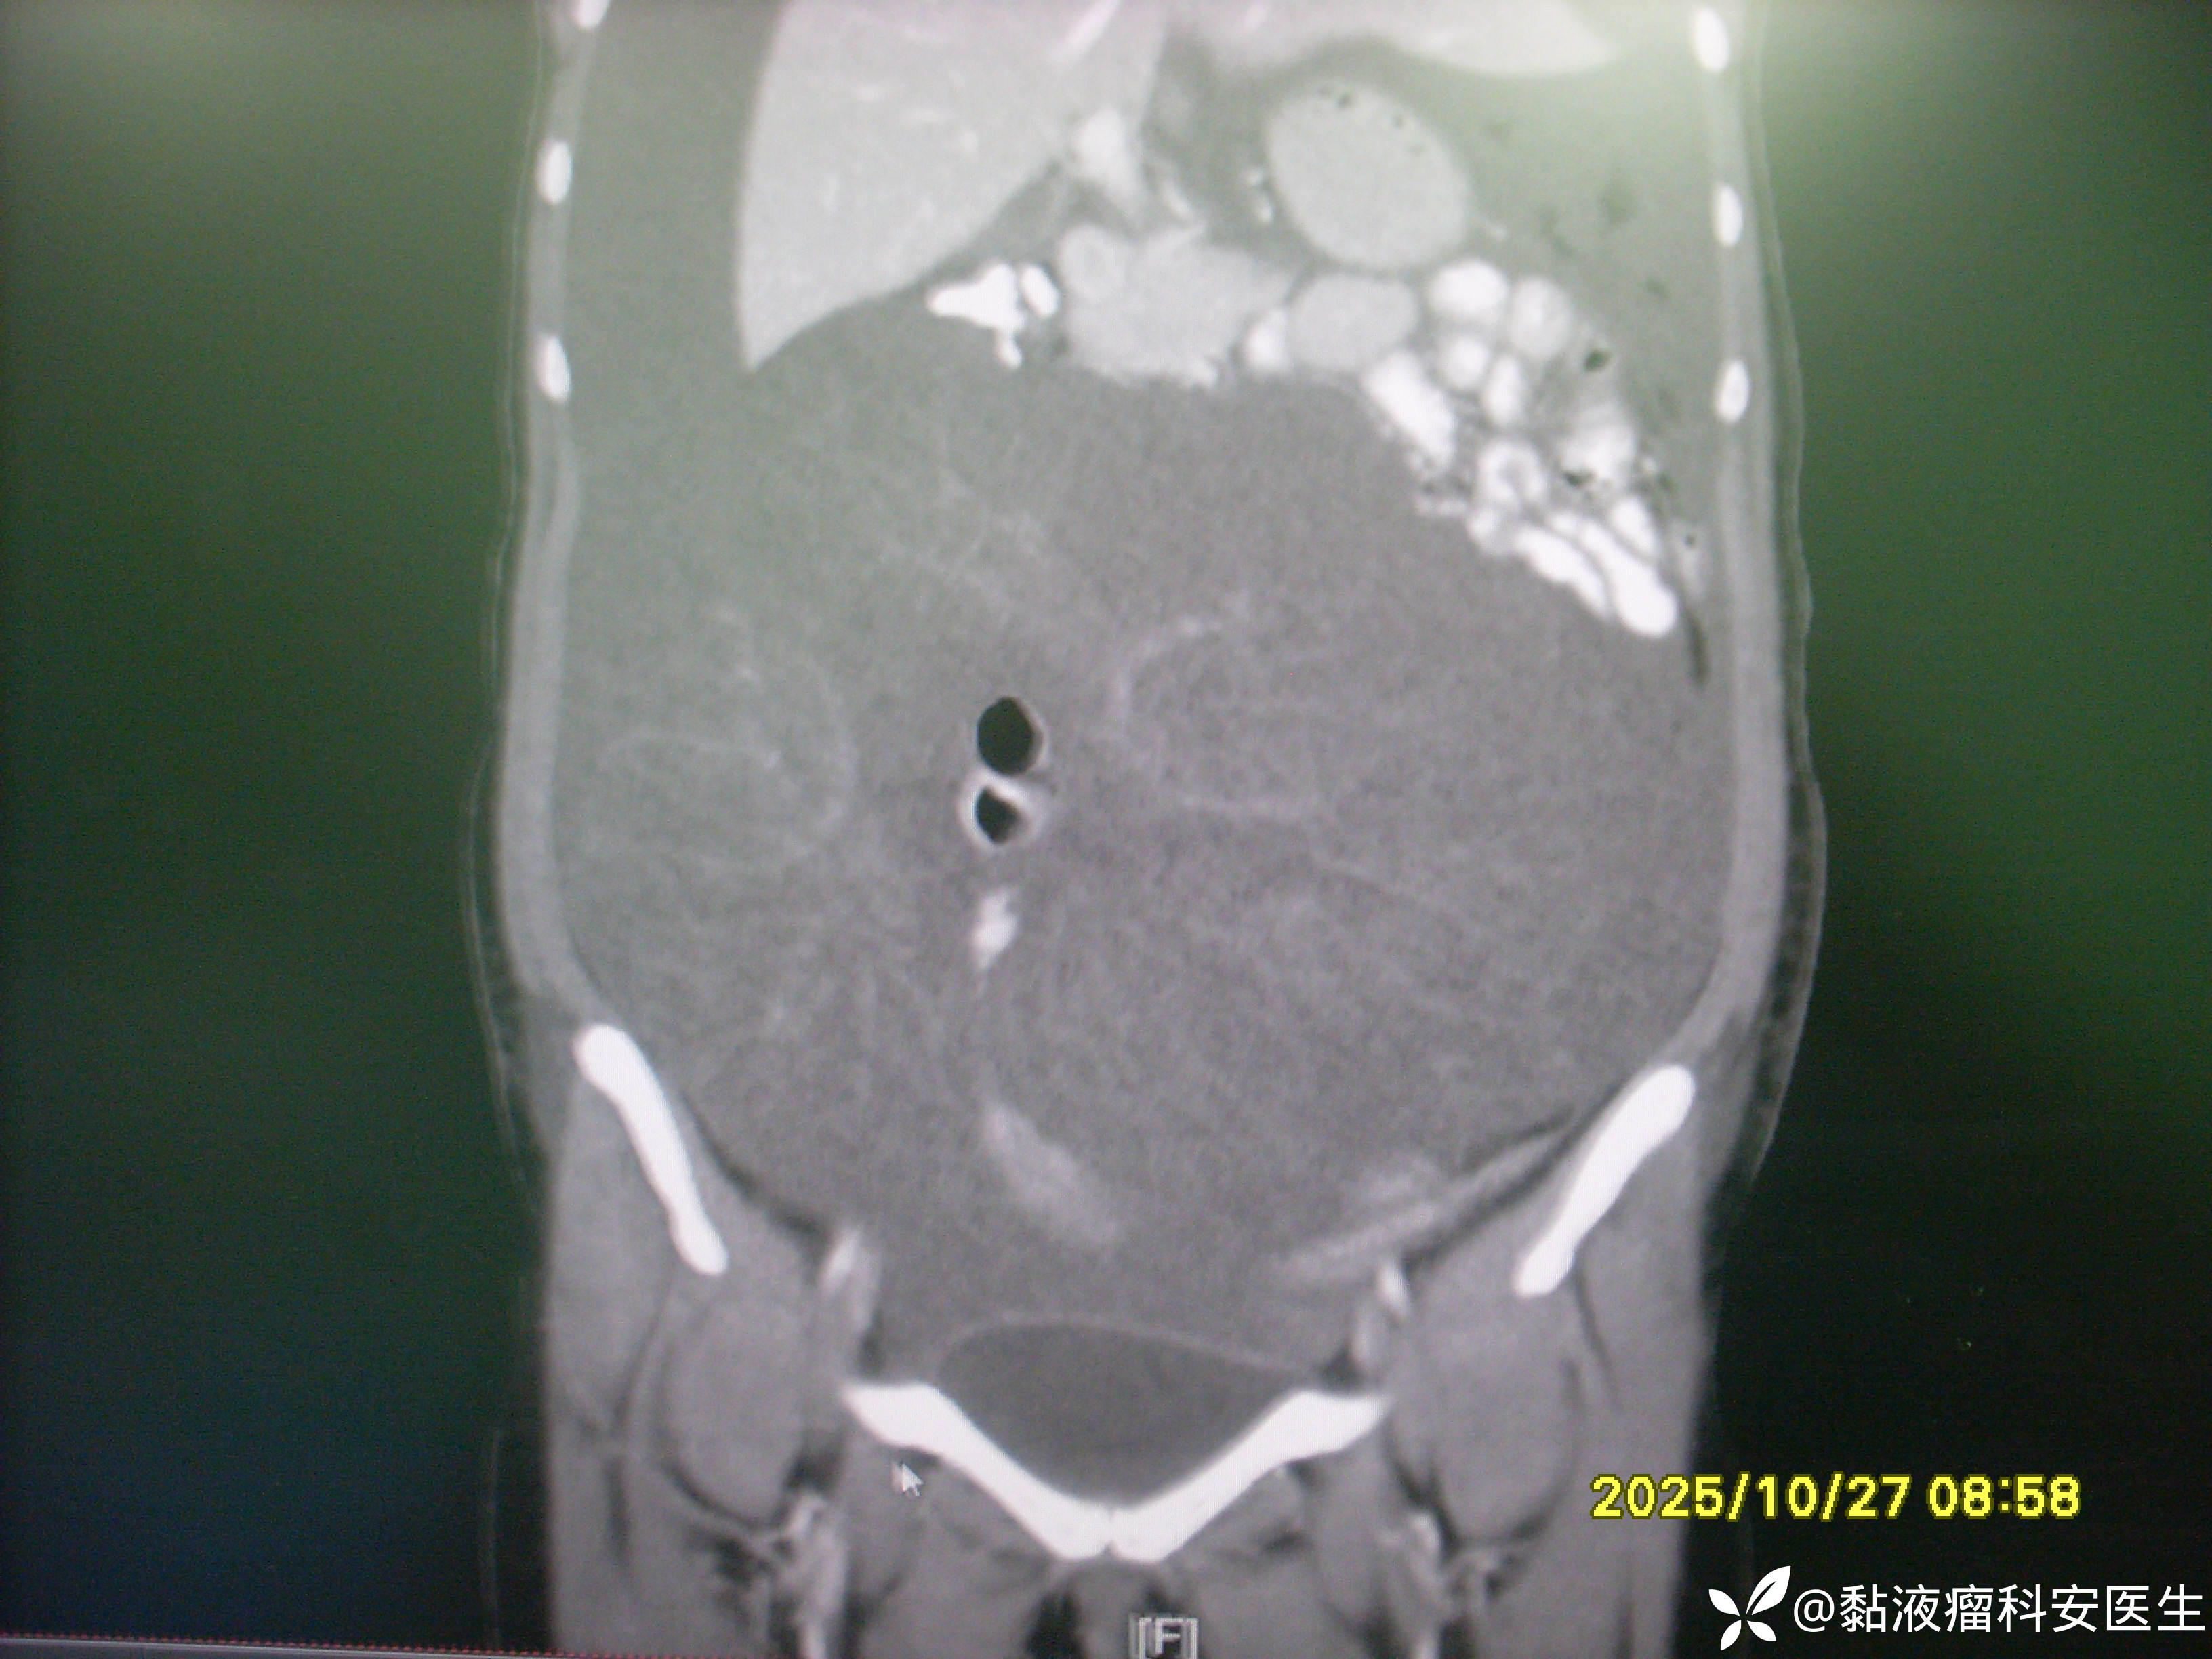

术前CT

腹腔巨大占位是什么?